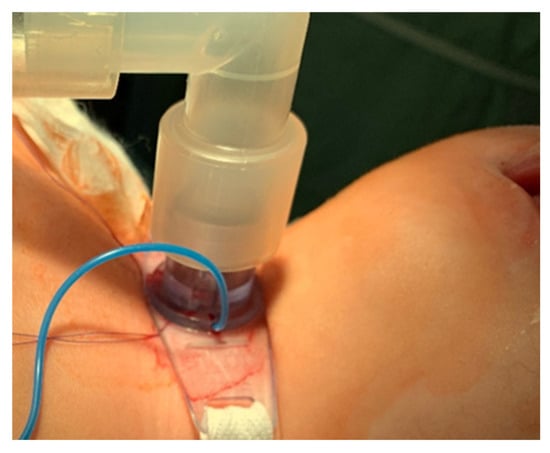

- Bipolar cautery is used during the procedure for hemostasis (Figure 4).